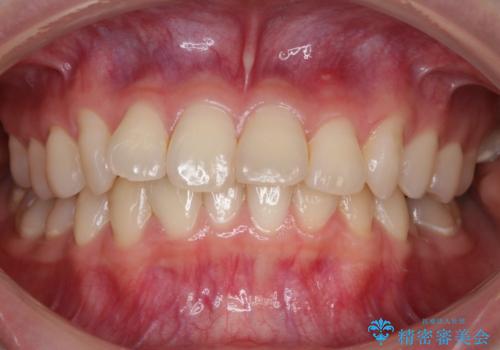

【非抜歯】結婚式に向けて矯正で素敵な笑顔を!

- 笑った時の歯の見え方を治したいとのことで矯正相談にいらっしゃいました。

一見そこまで大きなガタつきはないようにも見えますが、前歯の角度の不揃いや噛み合わせのズレなどから見え方に影響が出てしまっていました。

抜歯は全く必要のないレベルのガタつきだったため、マイクロインプラントを用いて歯全体を後方に移動させていくことできれいな歯並びを獲得することができました。